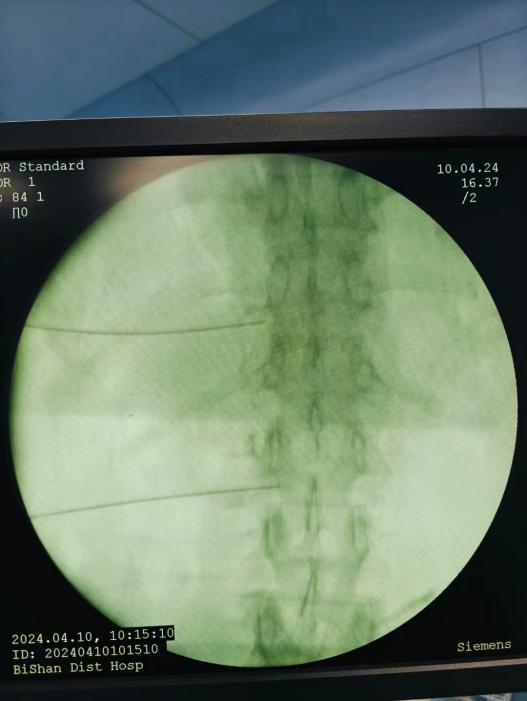

神經(jīng)阻滯,將藥物在影像引導(dǎo)下注射到受損神經(jīng)周圍,減輕炎癥和疼痛;

臭氧注射,通過向椎間盤內(nèi)注射臭氧,氧化髓核內(nèi)的蛋白多糖,降低椎間盤內(nèi)壓力,緩解癥狀;

射頻消融治療,連續(xù)射頻或脈沖射頻對椎間盤或神經(jīng)進(jìn)行干預(yù)治療,目的是減小神經(jīng)根周圍的壓力及對神經(jīng)的調(diào)控治療,從而達(dá)到緩解癥狀的效果;

膠原酶椎間盤化學(xué)溶解術(shù),是在影像引導(dǎo)下(C型臂X線機(jī)或CT),將膠原酶準(zhǔn)確地注射到突出的椎間盤內(nèi)及其周圍,使突出的椎間盤溶解并吸收,解除其對神經(jīng)根的壓迫,進(jìn)而緩解癥狀。

椎間盤射頻消融術(shù)、膠原酶椎間盤化學(xué)消融術(shù)